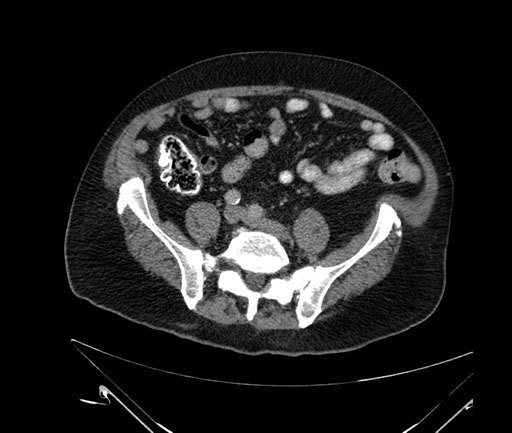

Imaging Analysis

Look through the patient's CT scan to identify any areas of concern for the necessary procedure.

Based on your CT findings, which issue(s) would give reason for "planned slowing down moment(s)" in this case?

Considering a standard Whipple procedure, what step(s) of the operation would you do differently in this case?